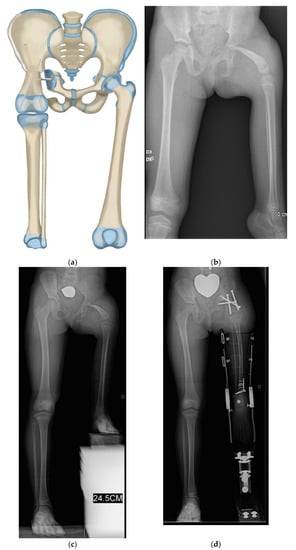

Figure 5.

(a) Illustration of CFD Paley type 3c. There is an ankylosed knee with a small distal femoral remnant. (b) Illustration showing the femoral head is enucleated to make room for the femoral condyle or tibial plateau in the acetabulum. (c) Paley–Winkelmann rotationplasty illustration, inserting the femoral condyle remnant into the acetabulum secured with a hip tethering suture. (d) AP pelvis radiograph of a 12-year-old girl with CFD Paley type 3c. (e) Standing long radiograph of same girl showing the ankle is at the level of the opposite knee. (f) AP pelvis radiograph of same girl after Paley–Winkelmann rotationplasty with femoral condyle in the acetabulum. The tethering suture anchor is seen. (g) Standing radiograph of same girl 5 years after Paley–Winkelmann rotationplasty. She has excellent function of the new hip joint and can walk and run with very minimal limp.